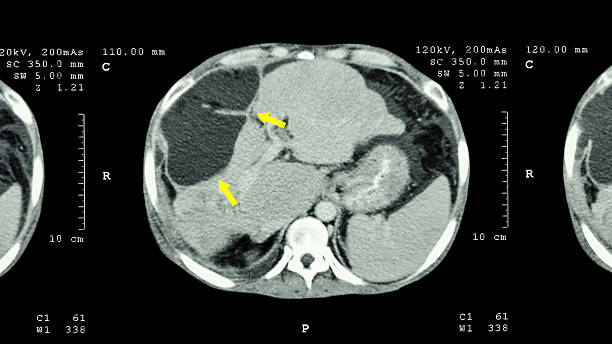

1. 전두엽 손상

뇌경색 후, 이마 부위에 손상이 생기면 하체의 힘이 약해질 수 있습니다. 이로 인해 환자는 걷거나 움직일 때 한 쪽으로 기울거나 반쪽의 마비가 발생할 수 있습니다. 대소변의 장애, 성격 변화, 사고력 저하, 집중력 감소 등과 같은 부작용도 나타날 수 있습니다.